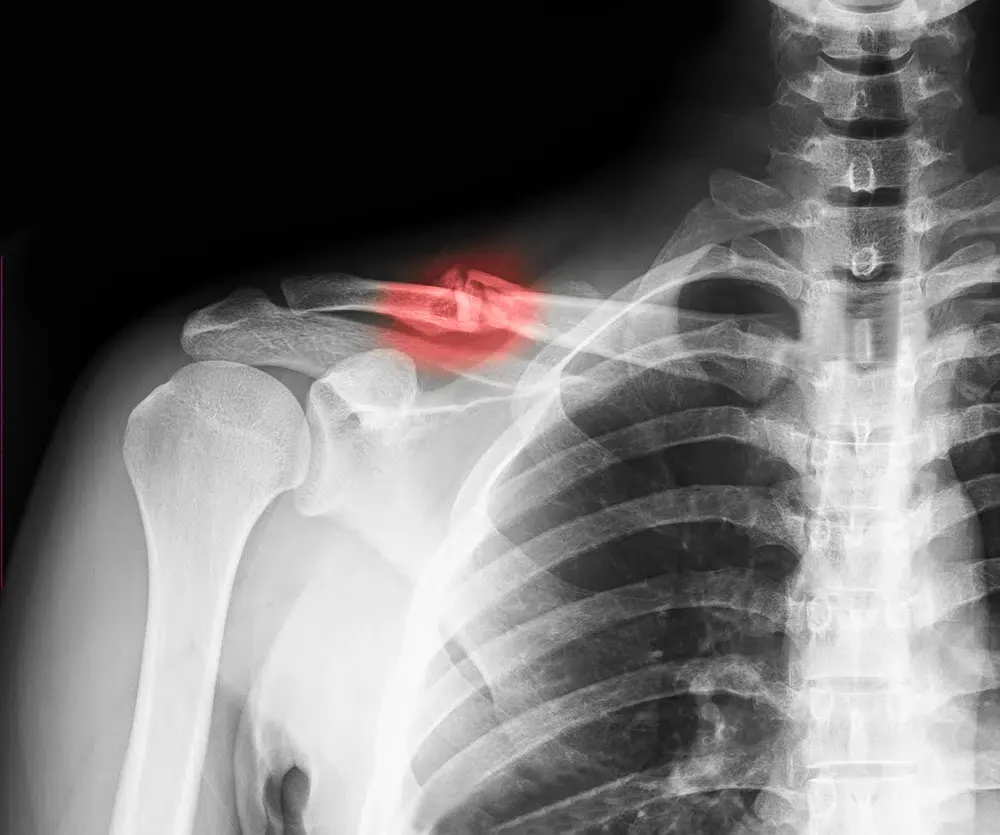

Your collarbone, the clavicle, supports shoulder function, but its position across the upper chest makes it vulnerable in crashes. Head on collisions, side impacts, and rollovers can transmit force through the seat belt, shoulder, or vehicle interior, leading to fractures that may require immobilization, physical therapy, or, in some cases, surgery.

This covers all past, present, and future medical bills associated with your injury, including Emergency room visits and doctor consultations. Imaging tests like X-rays, CT scans, or MRIs. Surgery and anesthesia costs, if necessary. Rehabilitation and physical therapy sessions. Pain medication and other prescriptions.